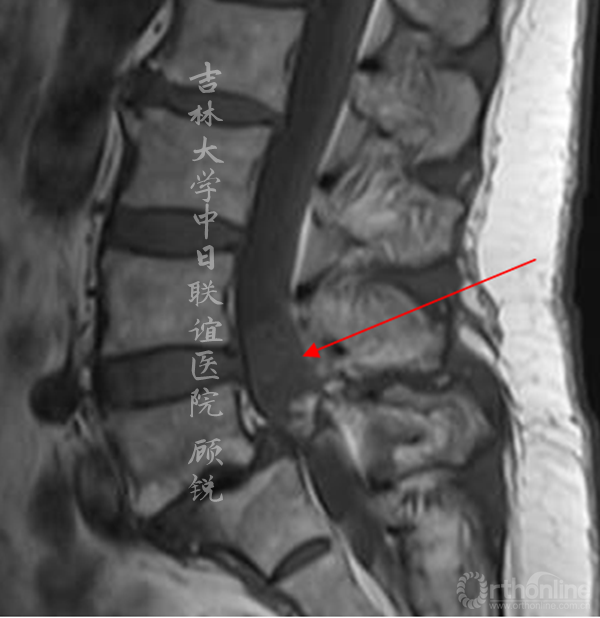

MRI平扫如下:

(L4-5)

滑脱椎体后方椎管内见异常信号,是游离髓核(硬膜内)?椎管内肿瘤(神经源性、转移)?血管畸形?还是其他其他?组内会诊认为以疾病一元论解释患者的症状、体征考虑因滑脱椎导致马尾神经冗余的可能性大。进一步检查了增强腰椎MRI。